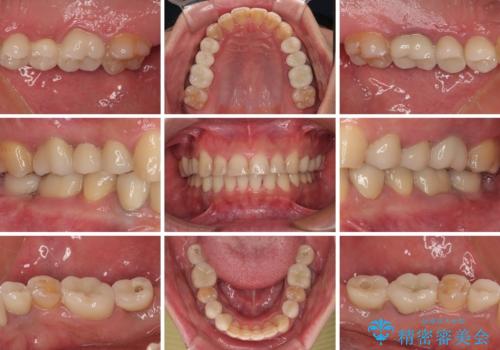

銀歯を白くしたい 一緒に矯正治療も行ない美しい口腔内に

- 近医にて下顎奥歯の抜歯が必要と言われたとのことで来院された患者様です。

診察の結果、奥歯は左右ともに抜歯が必要な状態でした。

他の銀歯も気になっており、セラミックにしたいとの要望があり、詳しくお話をすると、デコボコの歯ならびも整えたいとのことでした。

抜歯が必要な歯は事前に抜歯をし、その後ワイヤー装置にて歯列矯正を行い、途中でインプラントを埋入し、オールセラミッククラウンにて補綴治療を行うこととしました。

矯正治療にやや時間がかかりましたが、歯列はきれいに整い、気になっていたむし歯や銀歯は自然な色合いに仕上がりました。